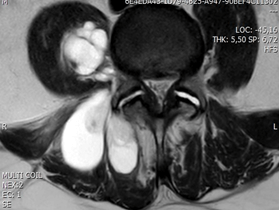

A pelvis MRI confirmed a multilobulated mass involving the right paravertebral muscles in the lower lumbar and sacral region that appeared hypodense on T1-weighted sequences and hyperdense in T2-weighted sequences (Figures 3 & 4).

Figure 4: Axial MR image of lumbosacral spine show contrast-enhanced of the lesion (T2 signal).